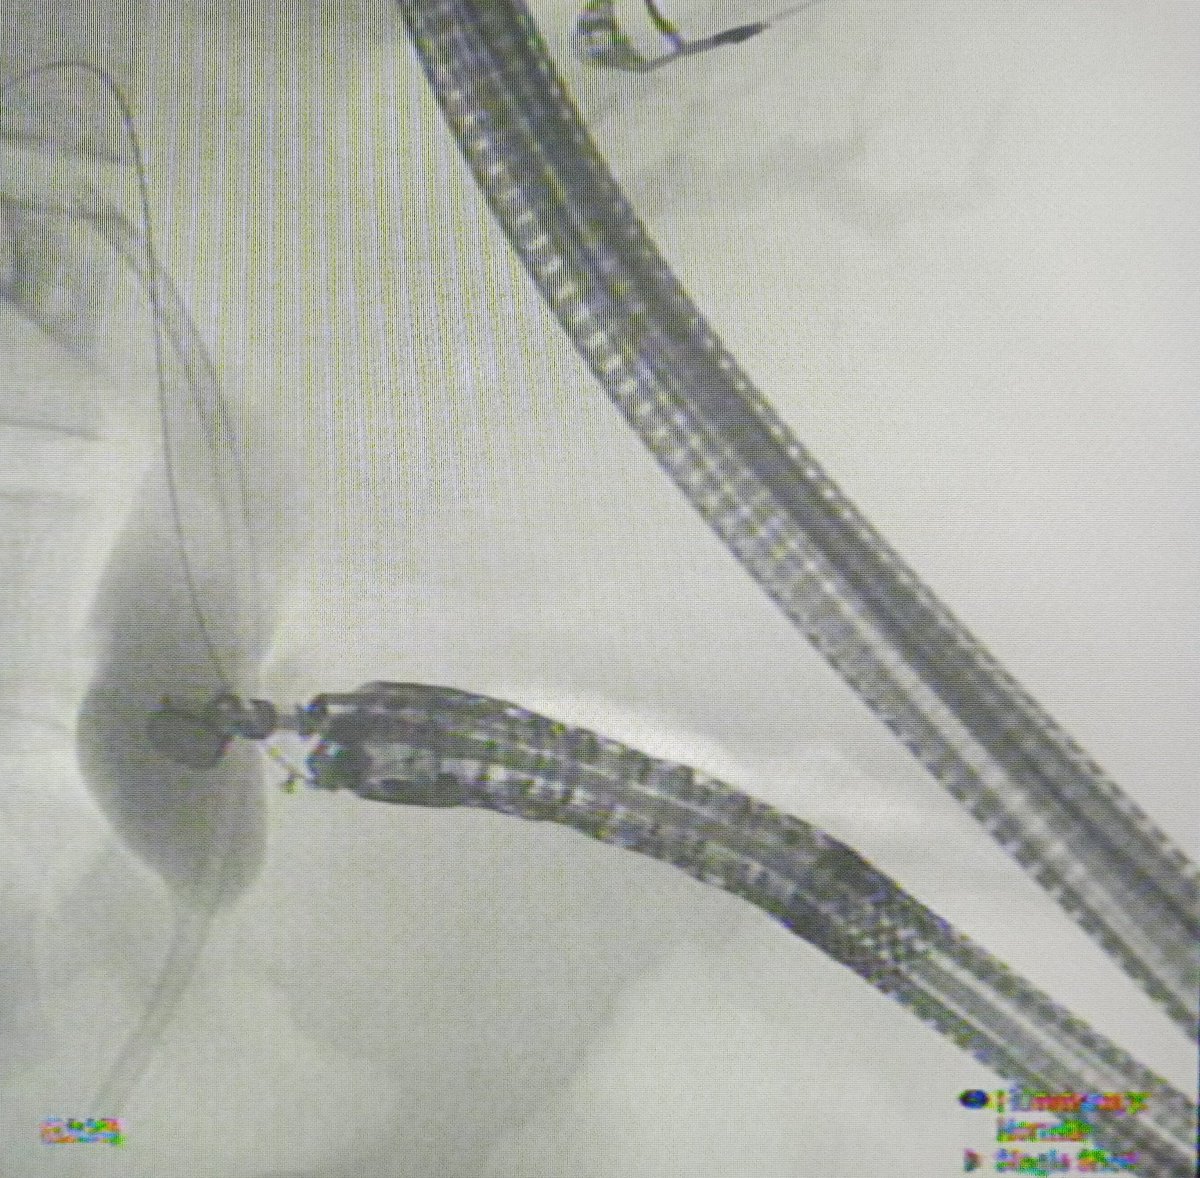

Yet another first for our centre and Rajasthan. First case of EUS guided Choledochoduodenostomy (CDS) done Department of Gastroenterology #AIIMSjodhpur @AIIMSJOfficial